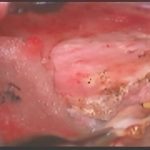

手術前1

摘出 前

摘出 中